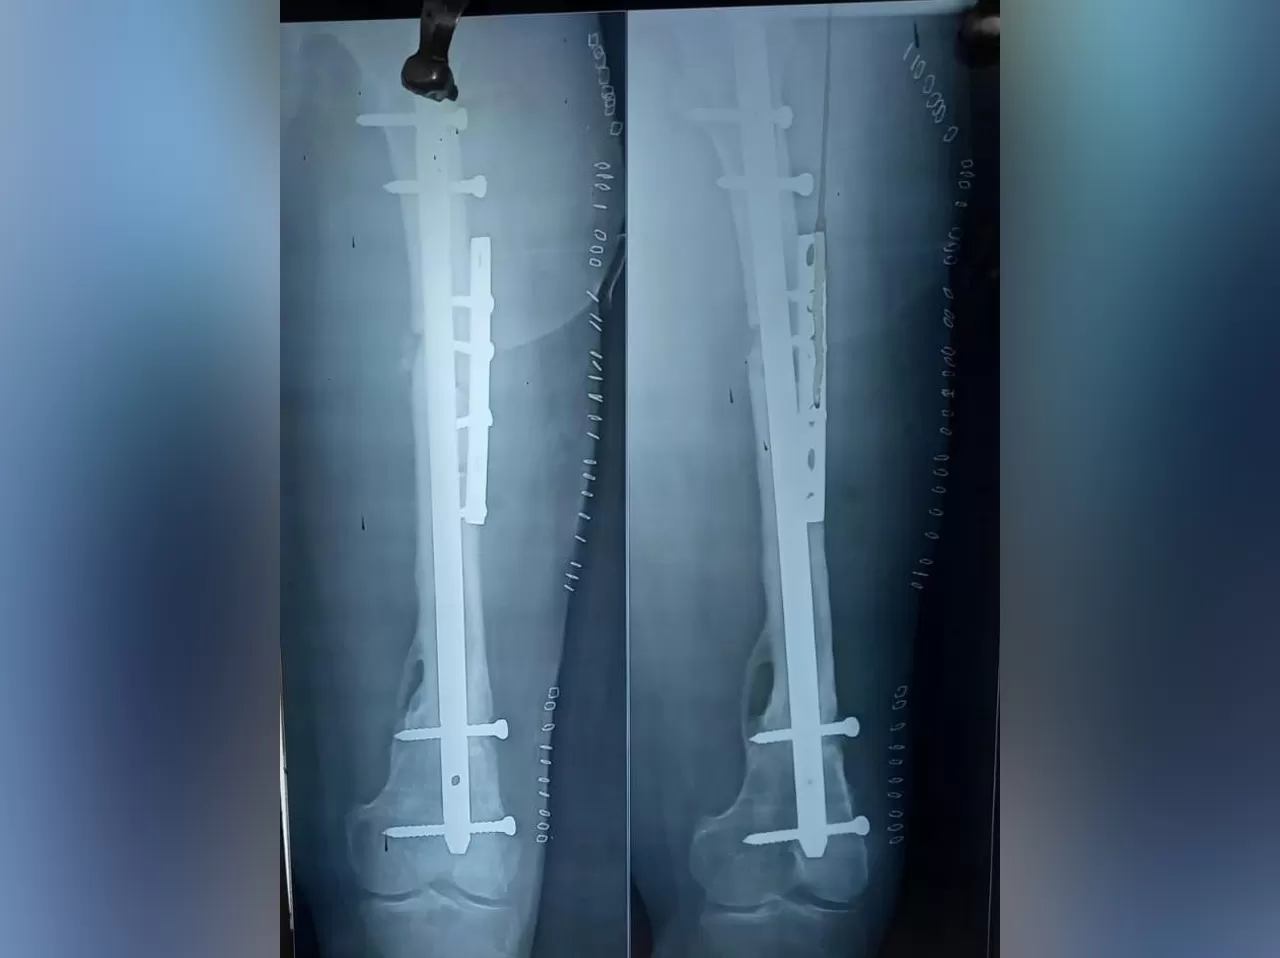

Mrs. Nazreen

Name: Mrs. Nazreen

Date of Operation: 09 Sep 2021

Age: 25 Years